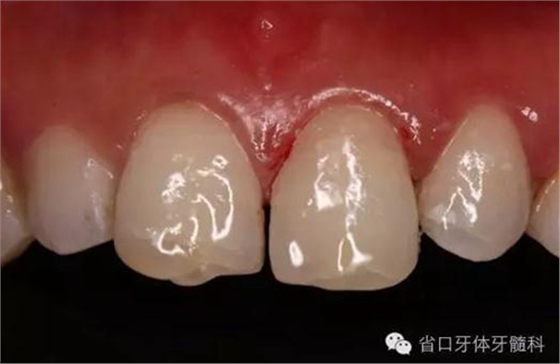

圖16. 術后口內(nèi)照

圖18. 術后23天隨訪的口內(nèi)照片